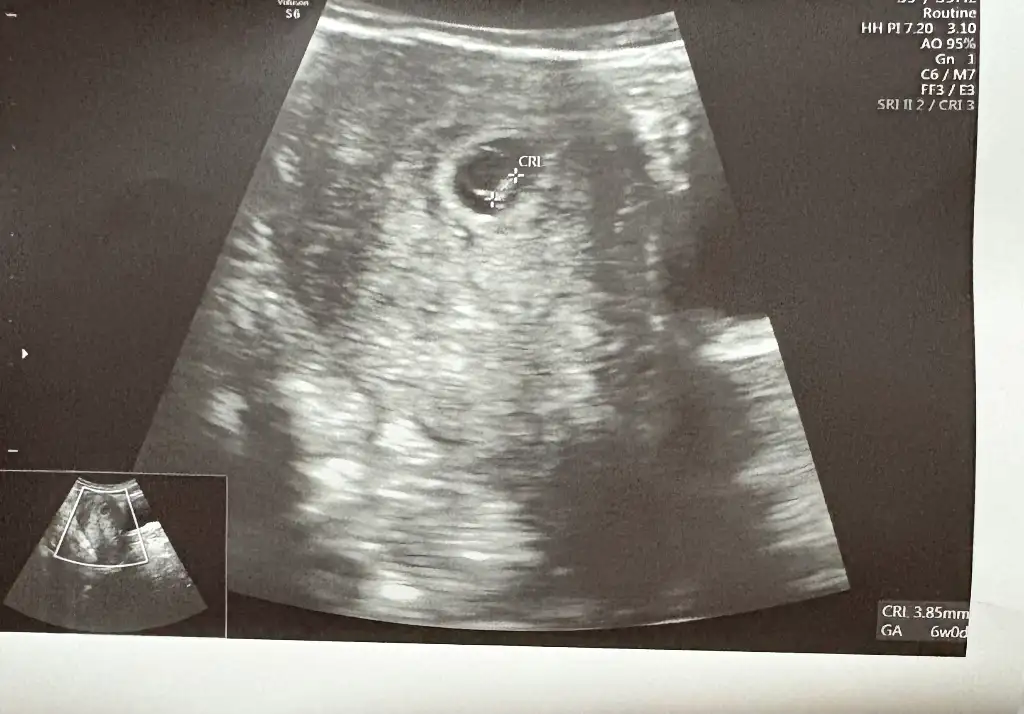

Kızlar ben dün kalp atışını duydum normalde 7 haftalık ama 6 haftalık gözüktü ultrasonda. Doktor Yolk kesesiyle ilgili bişey demedi ama ultrason kağıdında sanki çok büyük gözüküyo bi bakar mısınız sizde nasıl ?

Maşallah 🧿🧿🧿 Gerçekten büyük görünüyor maşallah. Ben de bugün kalp atışını duymaya gidiyorum 14:00'te randevum var 🥹💛 Darısı başıma inşallah duyarım